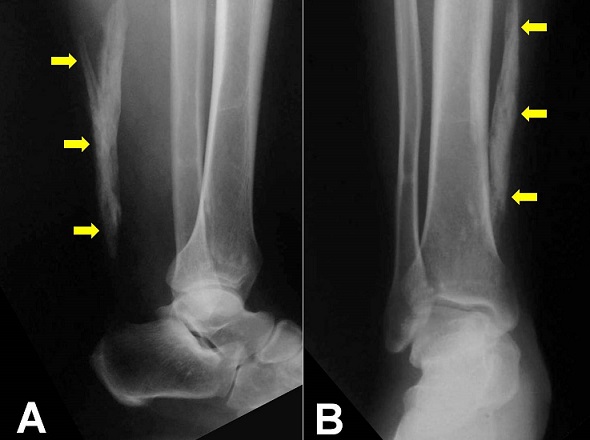

A 52-year-old man, previously healthy with no known metabolic or systemic illness, presented acutely following a direct trauma of the right foot. On examination there was soft tissue swelling and tenderness around the dorsum of the foot without neurological deficit. Plain radiography of the foot and the leg revealed a 10 centimeters ossification within the right Achilles tendon without fracture. The patient had no previous ankle problems. Local examination revealed a painless palpable gap and hard edges in the Achilles tendon but there are no disorders in walking. Because the patient was asymptomatic, no surgery was performed. Ossification of the Achilles tendon is an unusual clinical condition to be distinguished from the more frequently occurring tendon calcification. It is characterized by the presence of one or more segments of variable sized ossified mass within the fibrocartilaginous substance of the Achilles tendon. The etiology of this local ossification is unknown. The major contributing factors are trauma (especially repetitive microtrauma) and surgery with other minor causes such as systemic diseases, metabolic conditions, and infections. A large and extensive ossification for more than half of the tendon is rare and should not be misdiagnosed as a fracture or a foreign body particularly following an injury.